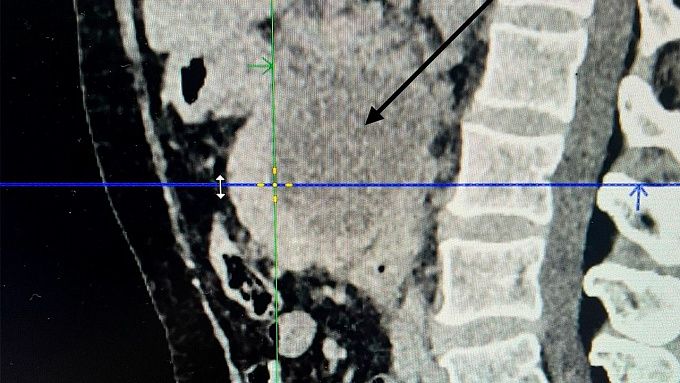

Женщину отправили в БСМП. Там хирурги провели малоинвазивную операцию под местной анестезией – дренирование кисты под УЗИ наведением.

- Сложность этой операции заключается в том, что поджелудочная железа располагается под желудком в сальниковой сумке, рядом располагаются толстый и тонкий кишечник. Нужно найти безопасное пространство, а это не так просто, чтобы не повредить желудок, толстый и тонкий кишечник, пройти иглой в полость кисты поджелудочной железы и по игле провести дренаж до 5 мм в диаметре, - отметил Андриан Тармаев.